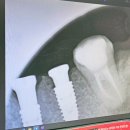

• 협진부분정비 | 강남역임플란트 vs 대학병원임플란트 가격비교 후 수술한 후기! 2개월 기록

위해 두번째 치료과정과 자세한 설명 참고하시라고 공유합니다 ^^ ​ ​ ​ 강남 임플란트 치과에서 임플란트와 뼈이식 추천 후기 지금으로부터 20년 전, 충치치료를 받고 금니를 해놓은 상태였는데 뭐든지 사용을 오래 하면 정비가 필요하... m.blog.naver.com 첫번째 포스팅 참고하세요^^ ​ ​ ​ 치과방문 ​ ​ ​ ​ 언제나 쾌적한...

쭈엄마의 일상(2025-09-17 12:33:00)